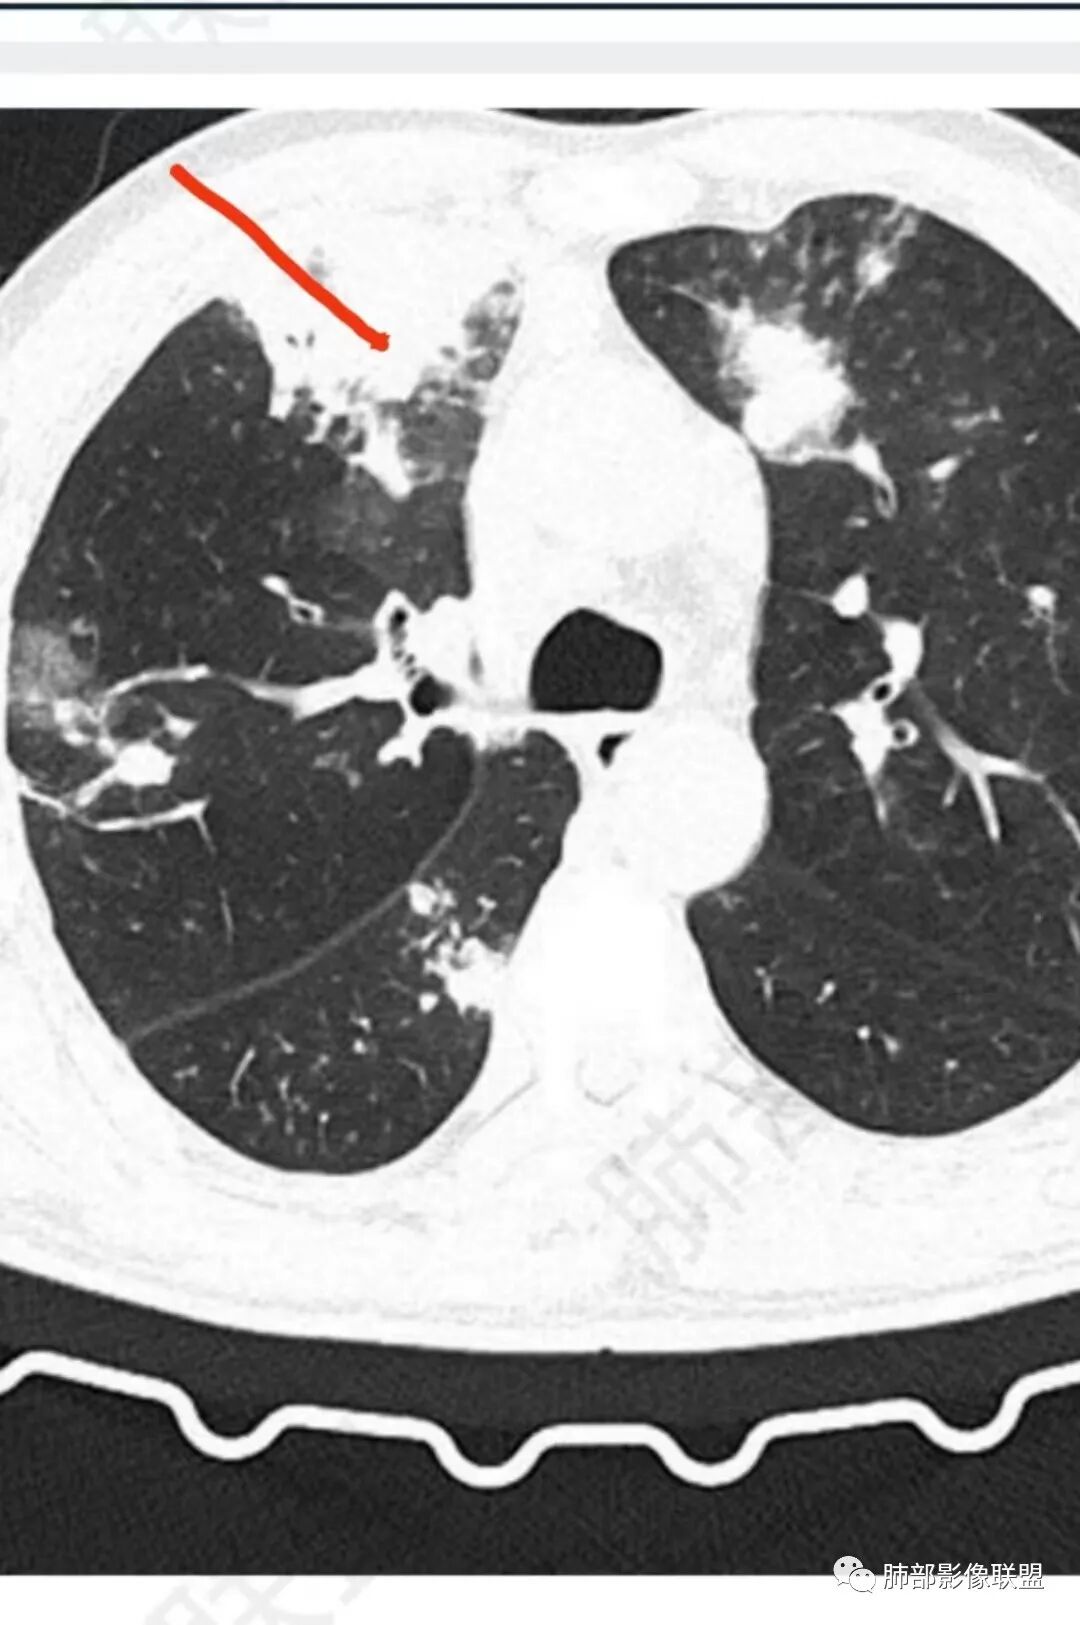

56岁,工作性质:环卫工人。主诉:咳、痰、喘、发病一周。急性起病(或者慢病+AE),呼吸道感染症状。化验指标白细胞、中性、CRP明显升高。影像学显示多灶性,有柱状支扩,囊状支扩等结构肺病,责任细菌主要考虑铜绿假单胞菌,不排除合并其他细菌以阴杆为主;存在树芽影,发热,炎症沿支气管束分布,是否合并TB?真菌?;树芽伴发热支原体感染也要需要考虑进去;全肺多灶性炎症,部分病灶周围有晕,右上叶疑似反晕,内部疑似有丝,右下肺考虑存在粘液栓,加之环卫工工作性质,考虑霉菌,主要考虑曲霉。

这样干净的支扩,不考虑曲霉及铜绿:

上面努卡之角,下面mei tai勾连